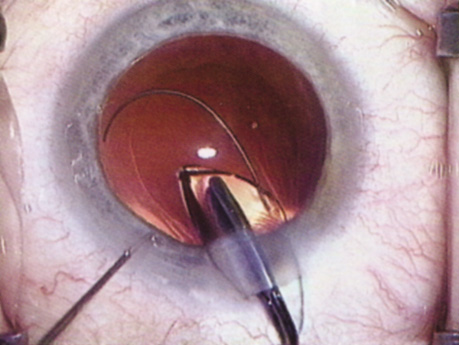

Patients who complain of glare from point sources of light, such as oncoming headlights or bright sunshine, may be best evaluated by a different form of glare testing. To simulate the environment of the patients' symptoms, Snellen acuity is measured while directing a point source of light obliquely toward the eye outside their best spectacle correction or outside of a phoropter dialed in with their best manifest refraction (Fig. 2).